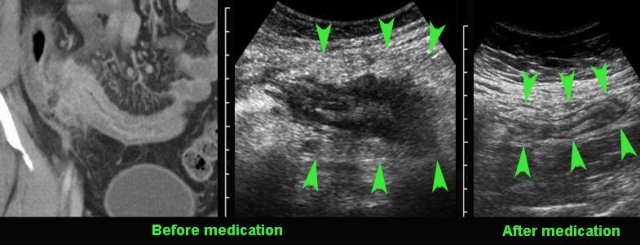

Compare the severely affected terminal ileum in this young patient with the US image after 8 months of medical therapy.

Note that both wall thickening and  the mass of acutely inflamed fat around the ileum did decrease (arrowheads).

Monitoring disease activity in response to medical therapy at the level of  the terminal ileum.

There is convincing decrease in wall thickening after 4 weeks of medication.

Note subtle residual hypoechoic, transmural changes (*) still visible  in the near wall after therapy.